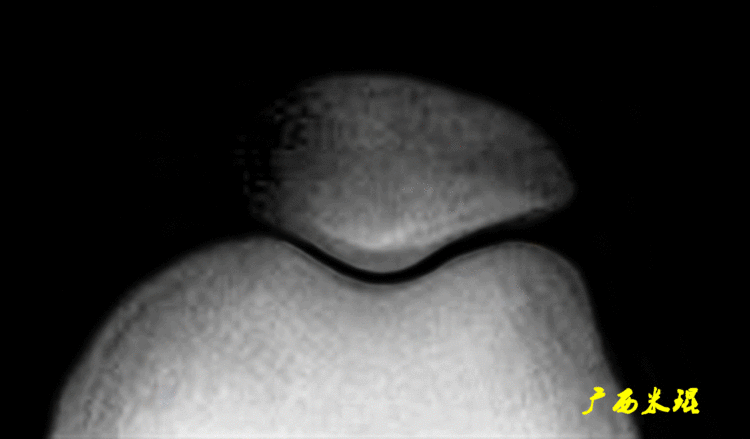

CT检查相对于DR检查,其主要优势在于其不仅不受体位影响,还可以动态观察膝关节伸屈活动中的髌股相对位置,能够提供髌骨不稳的准确信息,克服轴位X线片的不足,而且为了克服单层CT扫描中选点造成的测量误差,还可以使用图像叠加技术用于测量髌股关节排列关系,提高诊断率。

MRI检查是最常用的评估髌股关节软组织和滑车软骨的检查,在发现MPFL损伤时具有较高的敏感性和准确性,其特征性表现包括X线不能发现的软骨损伤及髌骨内侧面和股骨外侧髁的骨挫伤。MRI也可用于评估髌骨滑车指,测量髌骨高度等。